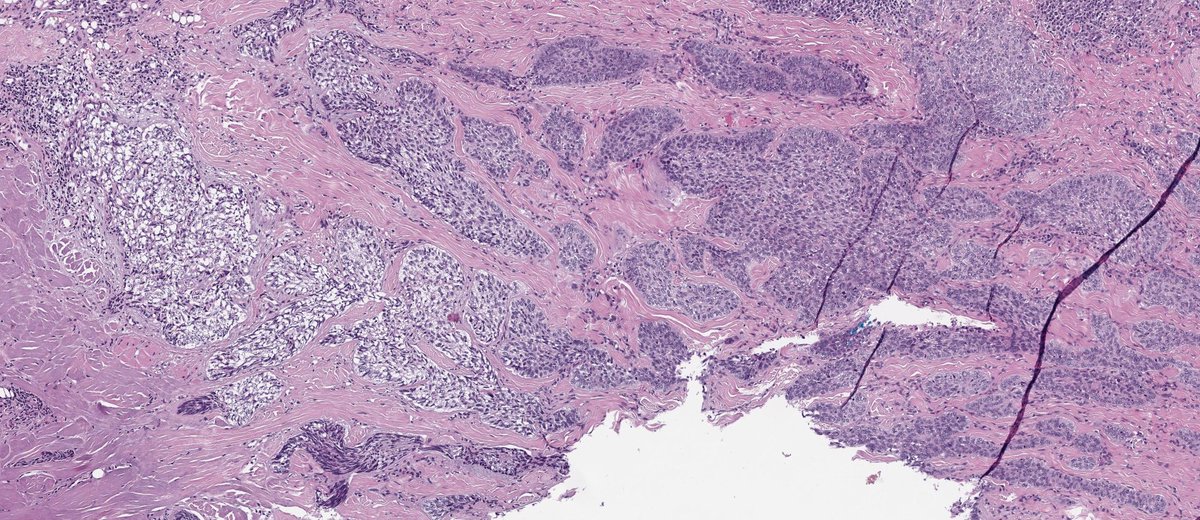

Nice reminder: Periadnexal invasion IS NOT exclusive to melanoma. Skin excision from a 26-year-old man. High-grade dysplastic nevus with adnexal invasion. Great mimic!! #dermpath #PathTwitter #dermtwitter

Nice reminder: Periadnexal invasion IS NOT exclusive to melanoma.

Skin excision from a 26-year-old man.

High-grade dysplastic nevus with  adnexal invasion.

Great mimic!!

#dermpath #PathTwitter #dermtwitter